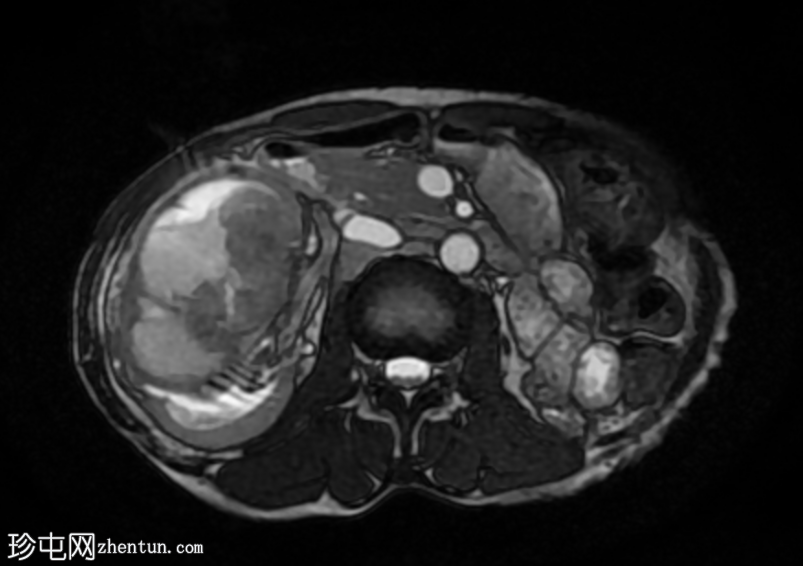

MRI

6.png

轴位

T2加权像

再次观察到上述肾前部外生性病变,其实性成分在T1加权像上呈等高信号,在T2加权像上呈低信号,伴有碎片扩散受限和低ADC值(化脓性物质)。囊性成分内部可见液-碎片/脓液界面。可见内部低信号结石。可见肾周模糊影。该病变压迫并可能侵犯右肾盂,导致中度肾积水。

病灶不规则的低信号,以及液-液界面伴有碎屑(可能为化脓性物质)扩散受限和肾周模糊,再次高度提示炎症性病变(黄色肉芽肿性肾盂肾炎,XGP),而非可能性较小的肿瘤。

左肾萎缩,体积较小,内含多发低信号结石。